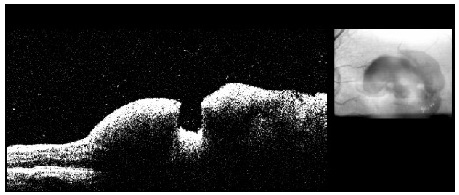

O OCT da lesão mostra espessamento da área com lumen vascular aumentado, podendo ser identificado e medido objetivamente o tamanho do macroaneurisma (figura 7).

Quando circundado por hemorragia, nota-se o contraste entre a área elevada e o macroaneurisma, semelhante a um vale entre dois cumes (figura 8).